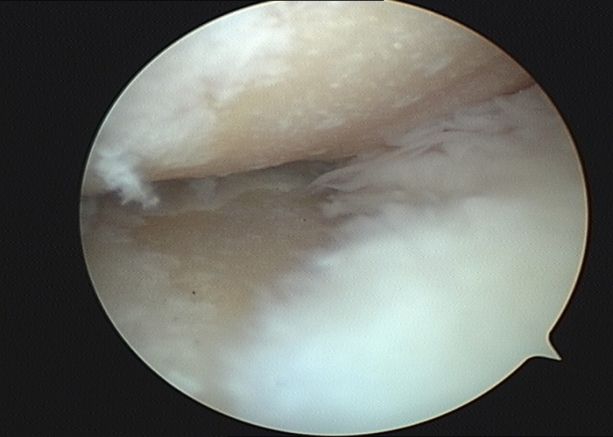

第三階梯:修復(fù)性治療。當(dāng)保守治療無法滿意控制病情時(shí),可考慮微創(chuàng)或矯形手術(shù)。①關(guān)節(jié)鏡清理術(shù):通過微創(chuàng)切口,清除關(guān)節(jié)內(nèi)的炎性滑膜、破碎的軟骨和游離體。②截骨術(shù):通過矯正下肢力線,將身體重量從磨損嚴(yán)重的一側(cè)轉(zhuǎn)移到相對(duì)健康的一側(cè)。